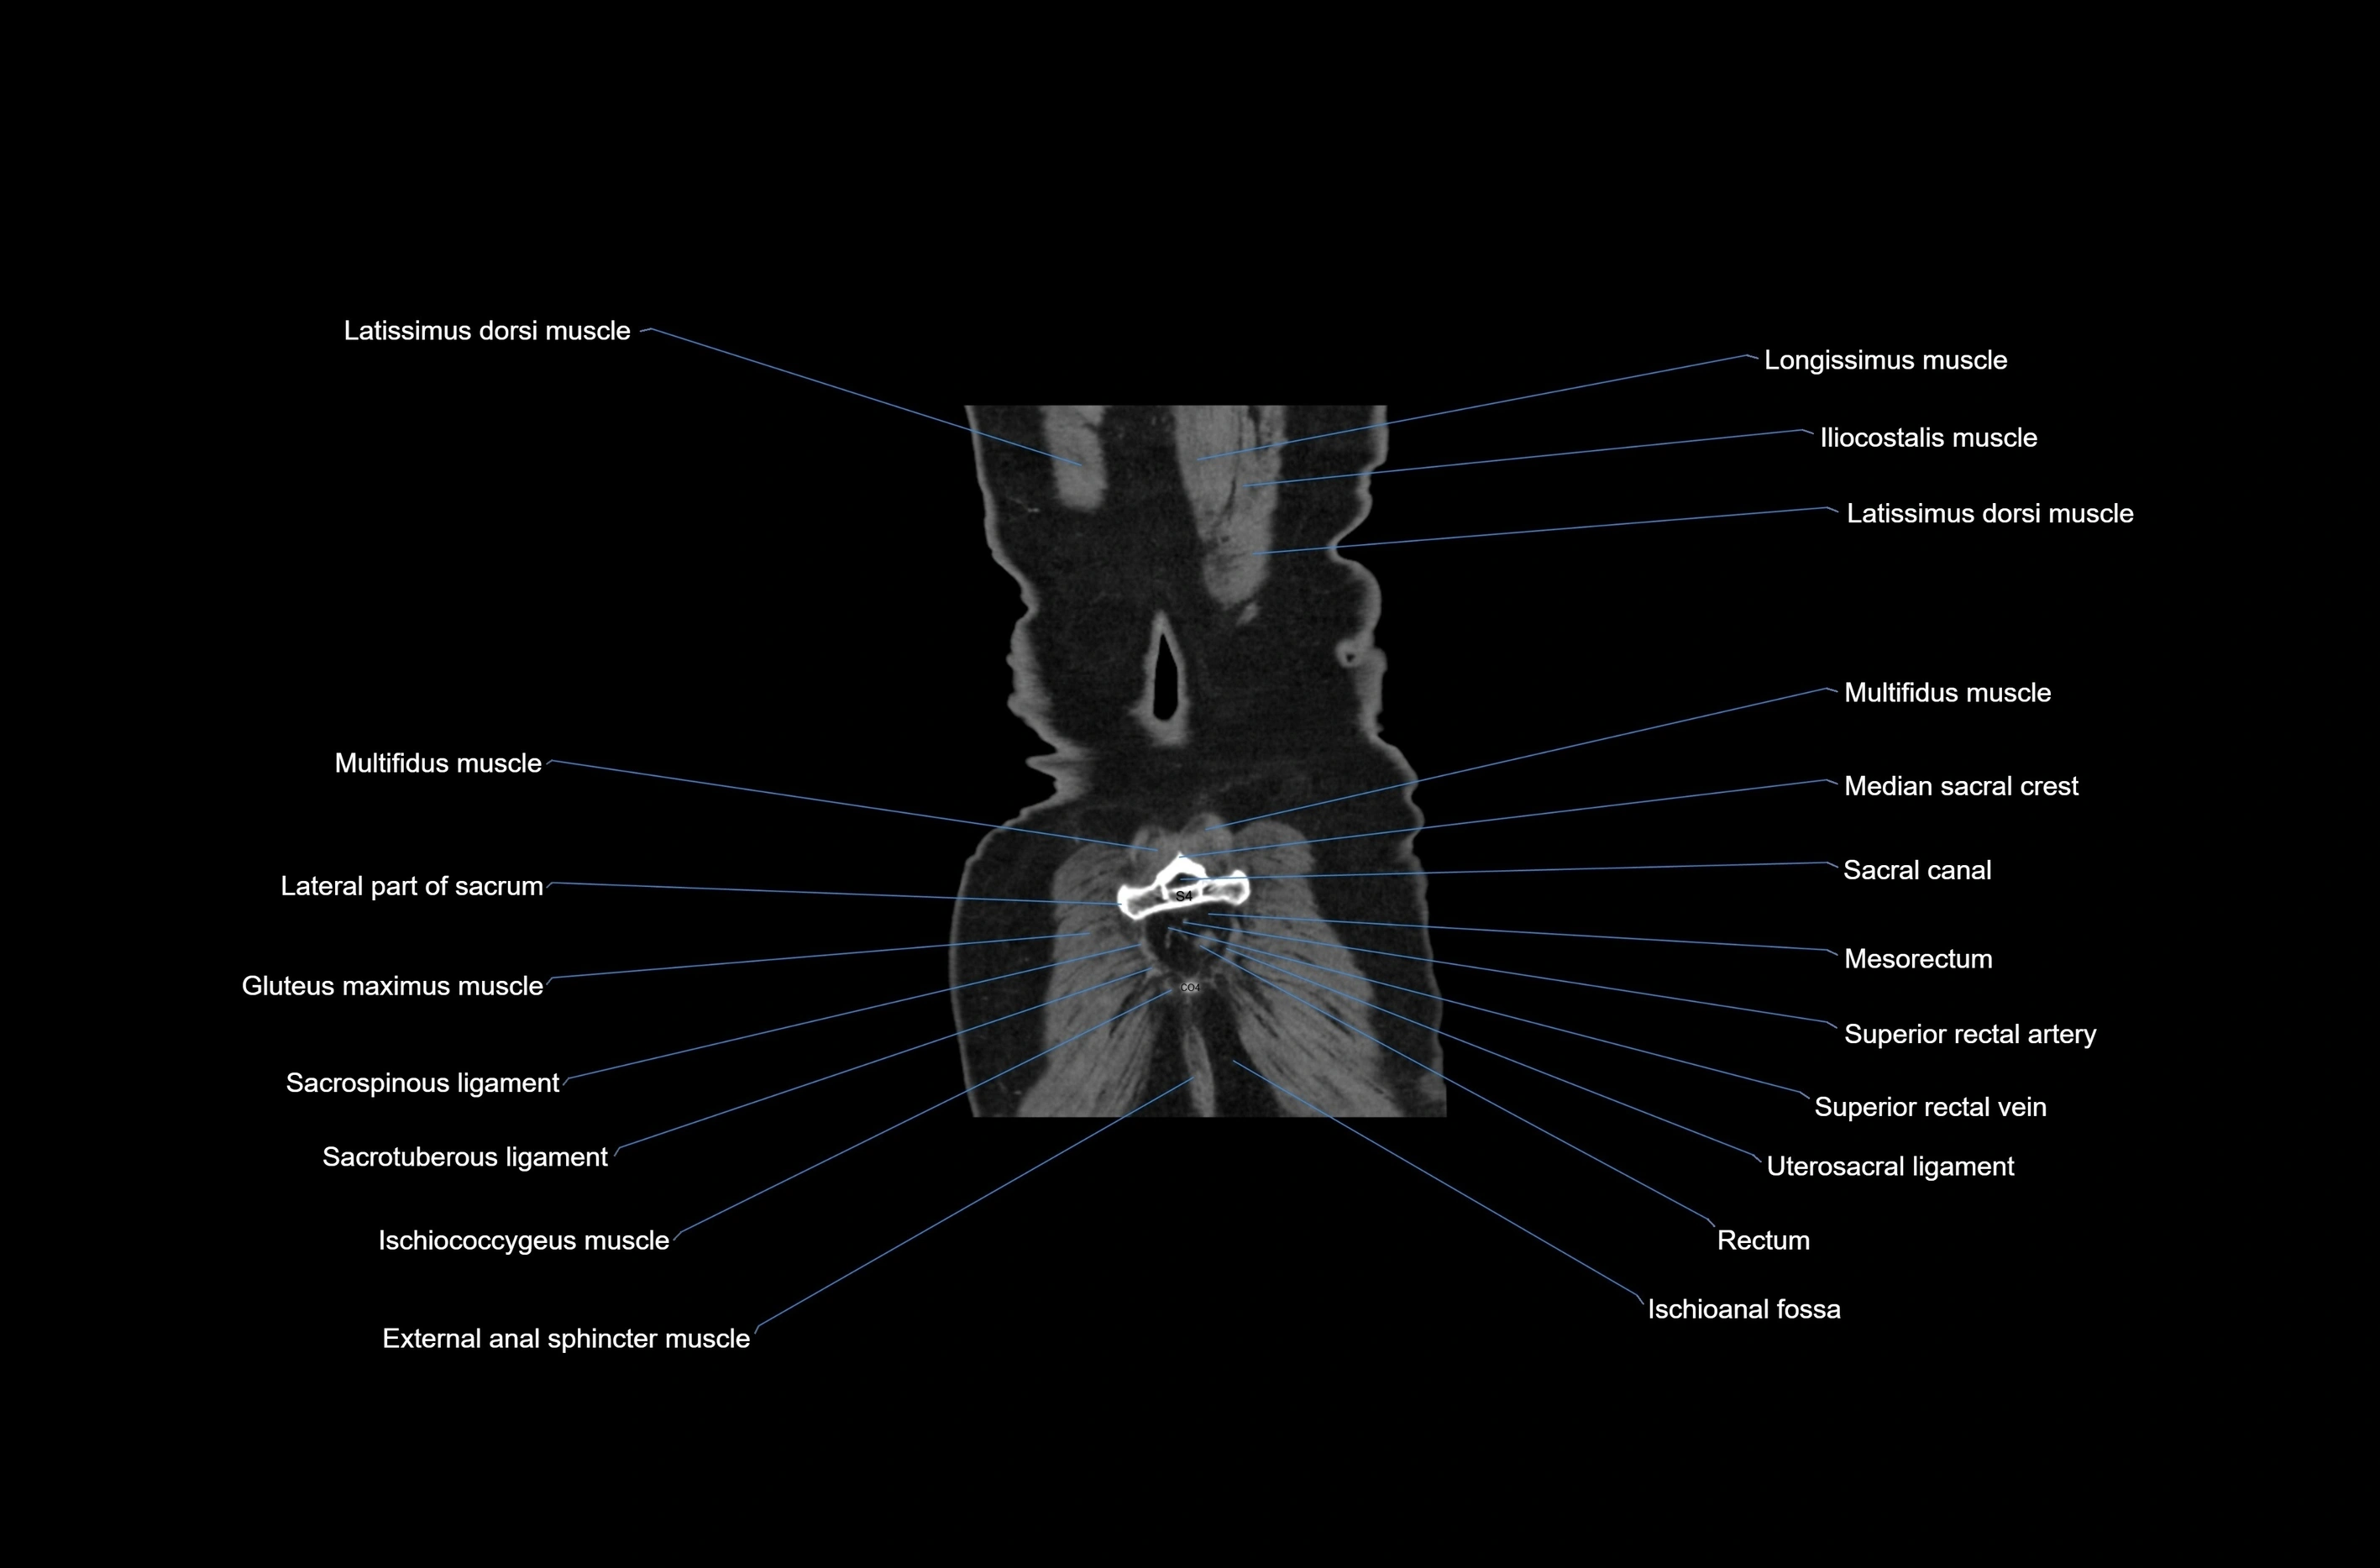

- Lateral part of sacrum

- Latissimus dorsi muscle

- Median sacral crest

- Sacral canal

- Mesorectum

- Superior rectal artery

- Superior rectal vein

- Uterosacral ligament

- Rectum

- Ischioanal fossa

- Gluteus maximus muscle

- Sacrospinous ligament

- Sacrotuberous ligament

- Ischiococcygeus muscle